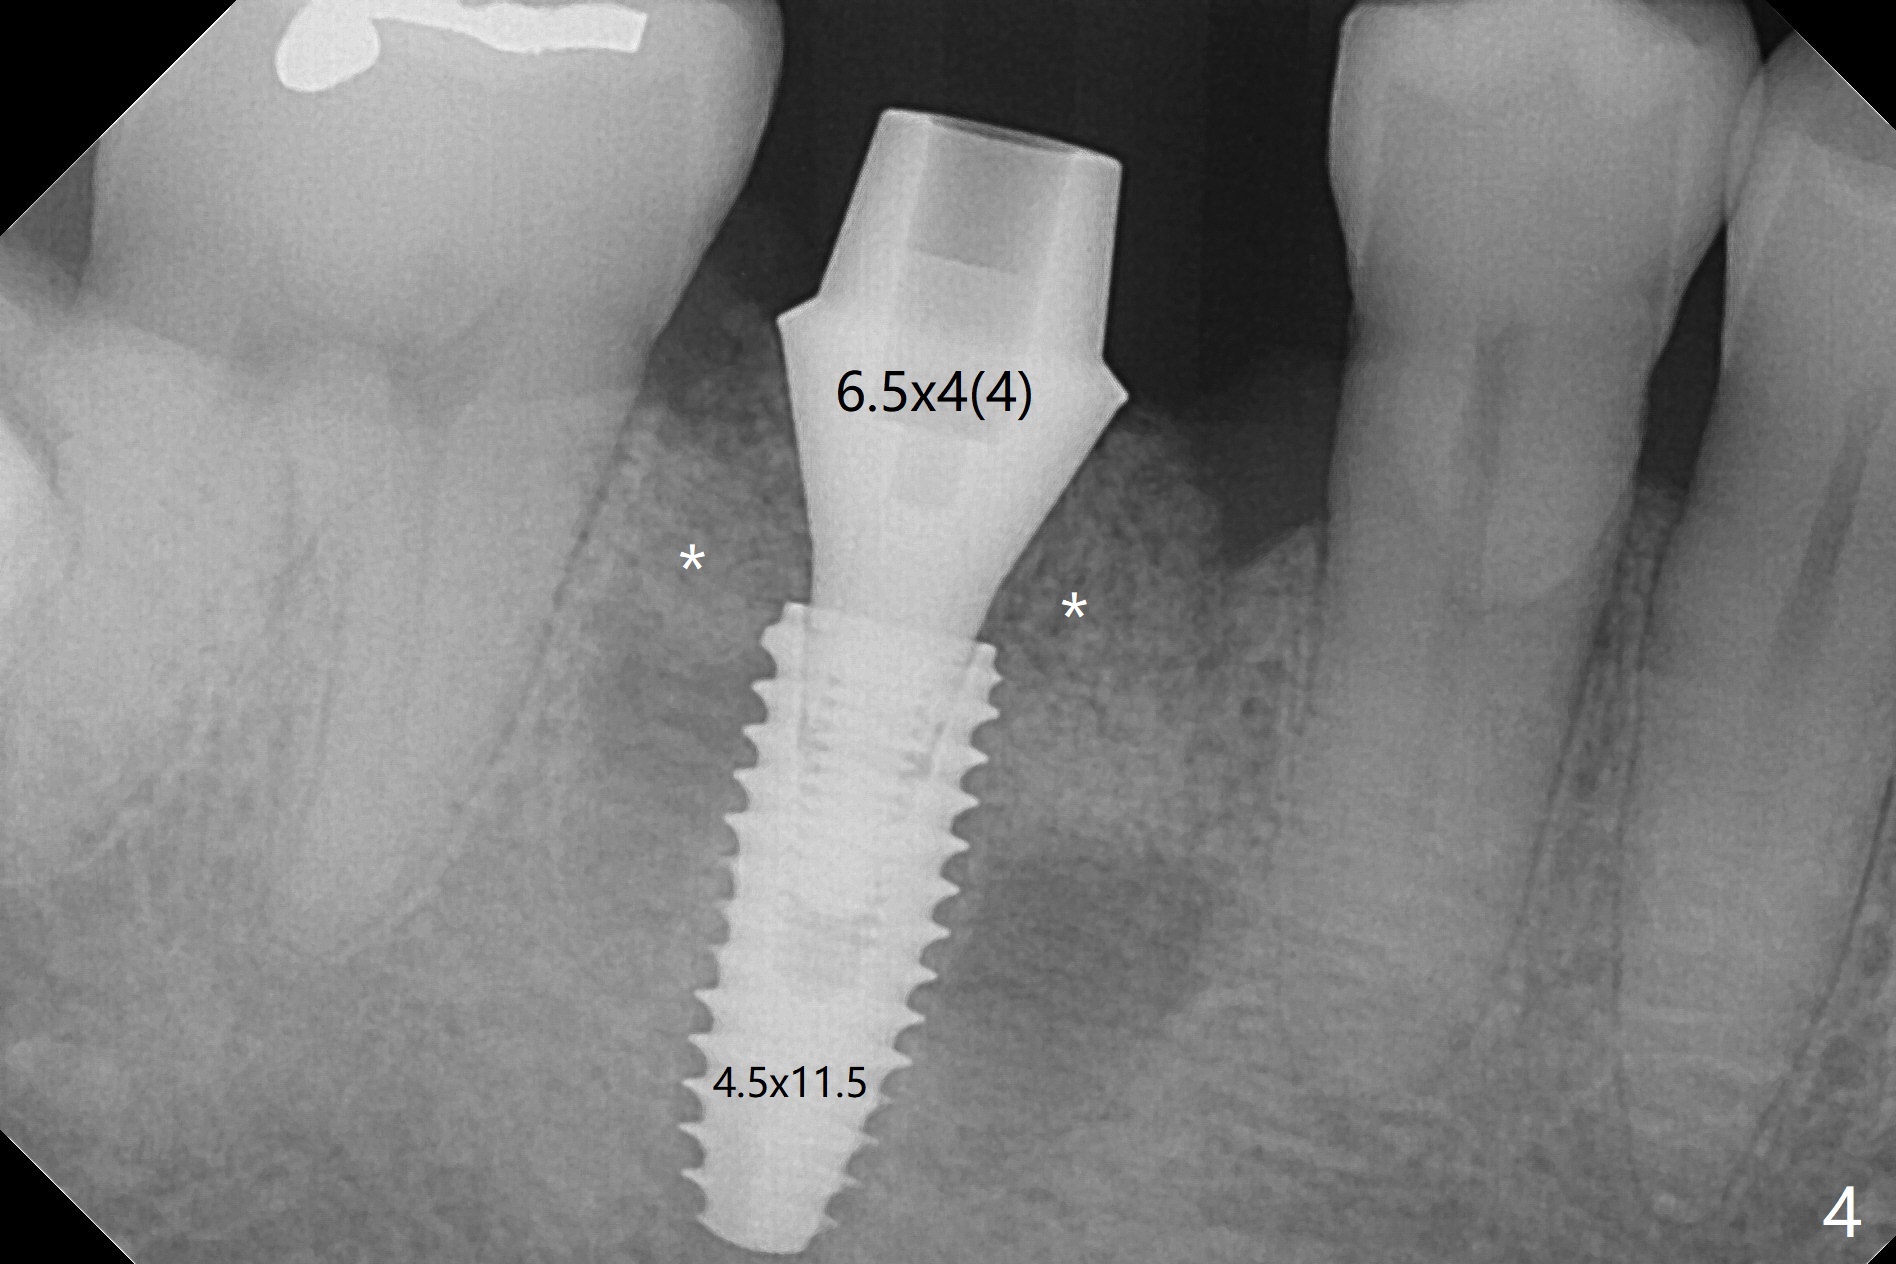

After extraction of the tooth #30, the mesiobuccal plate is found to be lost, corresponding to the fistula (Fig.1 <). Osteotomy is initiated in the flattened septum (lingual) for 13 mm (Fig.2). The patient feels pain when larger drills are being used. Marcaine has to be injected in an infiltration manner for pain control. When a 4.5x10 mm dummy implant is inserted with 55 Ncm, the end of the osteotomy (Fig.3 white line) is close to the Inferior Alveolar Canal (red dashed line). When a definitive implant (Fig.4: 4.5x11.5 mm) is placed with primary stability, there is an apical space (Fig.5 white double arrows). There is moderate postop pain. A shorter implant (10 mm) should be tried when the bone is dense. It will be associated with less pain. The fistula disappears 7 days postop (Fig.6). Although the patient appreciates that the pain is gone, there is atrophy mesiobuccally 2 months postop (Fig.7 *). The implant seems to be have been placed too buccally (Fig.8). With loss of the buccal plate, the implant should be placed away from it to prevent periimplantitis. The abutment is changed from 6.5x4(4) to 6.5x5.5 (3) mm with fabrication of a new provisional. The buccal margin is still supragingival 6 months postop and prep lower before impression. The mesial and distal sockets appear to have healed (Fig.9). When the crown is cemented, the mesiobuccal papilla is present (Fig.10 *), while the mesiolingual one is apparently absent (Fig.11 *). Using a temporary abutment and relining the provisional multiple times would increase the chance of rebuilding the missing papilla. The bone density around the implant increases 11 months post cementation (Fig.12). The dense (apparently cortical) bone seem to grow over the implant plateau 11 months post cementation (Fig.13 <).